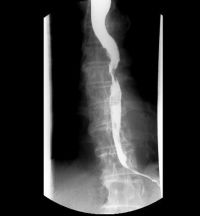

- X线食管钡餐检查:此为最基本的常规检查。此法检查简单、无痛苦、符合率高。检查可观察食管的蠕动状况、管壁的舒张度、食管黏膜改变、食管充盈缺损和梗阻程度。食管蠕动停顿或逆蠕动,食管壁局部僵硬不能充分扩张,食管黏膜紊乱、中断和破坏,食管管腔狭窄,不规则充盈缺损、溃疡或瘘管形成及食管轴向异常等均为食管癌的重要征象。低张双重造影对早期食管癌的检出较常规造影更有效。